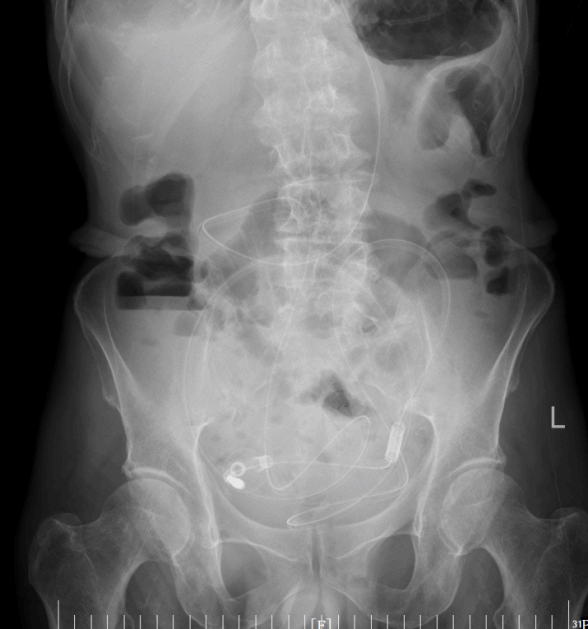

导管开始工作后,积聚的肠内容物被持续引出,腹胀腹痛的症状一天天缓解。老人的肠道功能慢慢恢复,复查腹平片显示梗阻情况明显好转。在护理团队的精心照料下,老人从卧床不起到能下地活动,从禁食禁水到逐渐恢复饮食,一天天好起来。2月24日,王大爷顺利出院,重新回归了正常生活。